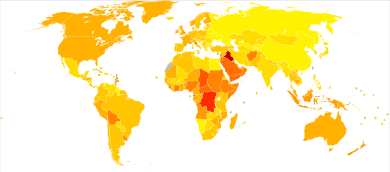

Globally, multiple myeloma affected 488,000 people and resulted in 101,100 deaths in 2015.[7][8] This is up from 49,000 in 1990.[13]